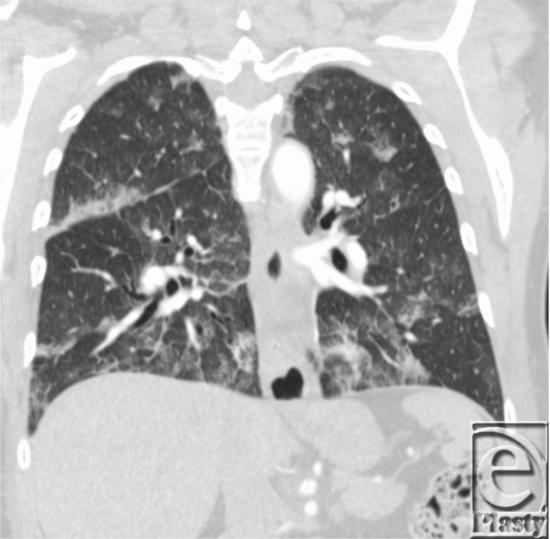

Hypoxia after abdominal and thigh liposuction: pulmonary embolism or fat embolism?

摘要